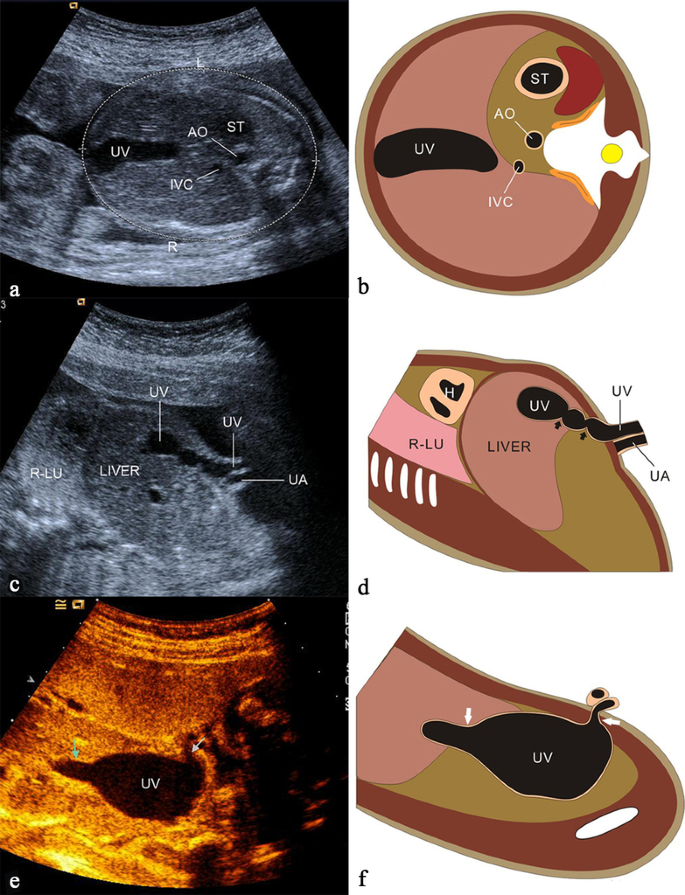

Umbilical vein varix (normal direction)

Umbilical vein varix (UVV) accounts for 4% of the malformations of the umbilical cord in the fetus with an incidence of 0.4–1.1/1000 [35]. UVV was defined as a portion of umbilical vein that is at least 50% wider than the non-dilated portion, a dilatation of ≥ 9 mm or dilatation of > 2SD above the mean value for gestational age [36]. The weak supporting structure of the UV contributes to the formation of UVV [37]. Sonographically, UVV appears as whole course ectatic anechoic UV or limited mass (Fig. 10), and color Doppler sonography detects the bidirectional turbulent flow, at the level of the dilated segment of the umbilical vein [35]. The main complications of UVV are intrauterine fetal demise (IUFD), thrombosis and intrauterine growth restriction (IUGR) with the total incidence of 10% [35]. The fetuses with isolated UVV have a very low likelihood of having associated chromosomal anomalies [36]. While compared with fetuses with isolated UVV, the incidence of chromosomal anomalies and the risk of IUFD for non-isolated UVV is 15-fold and eightfold, respectively [36]. A systematic structural examination should be performed, especially for the fetus with UVV diagnosed in the early pregnancy, and genetic testing is recommended in the fetus with non-isolated UVV.